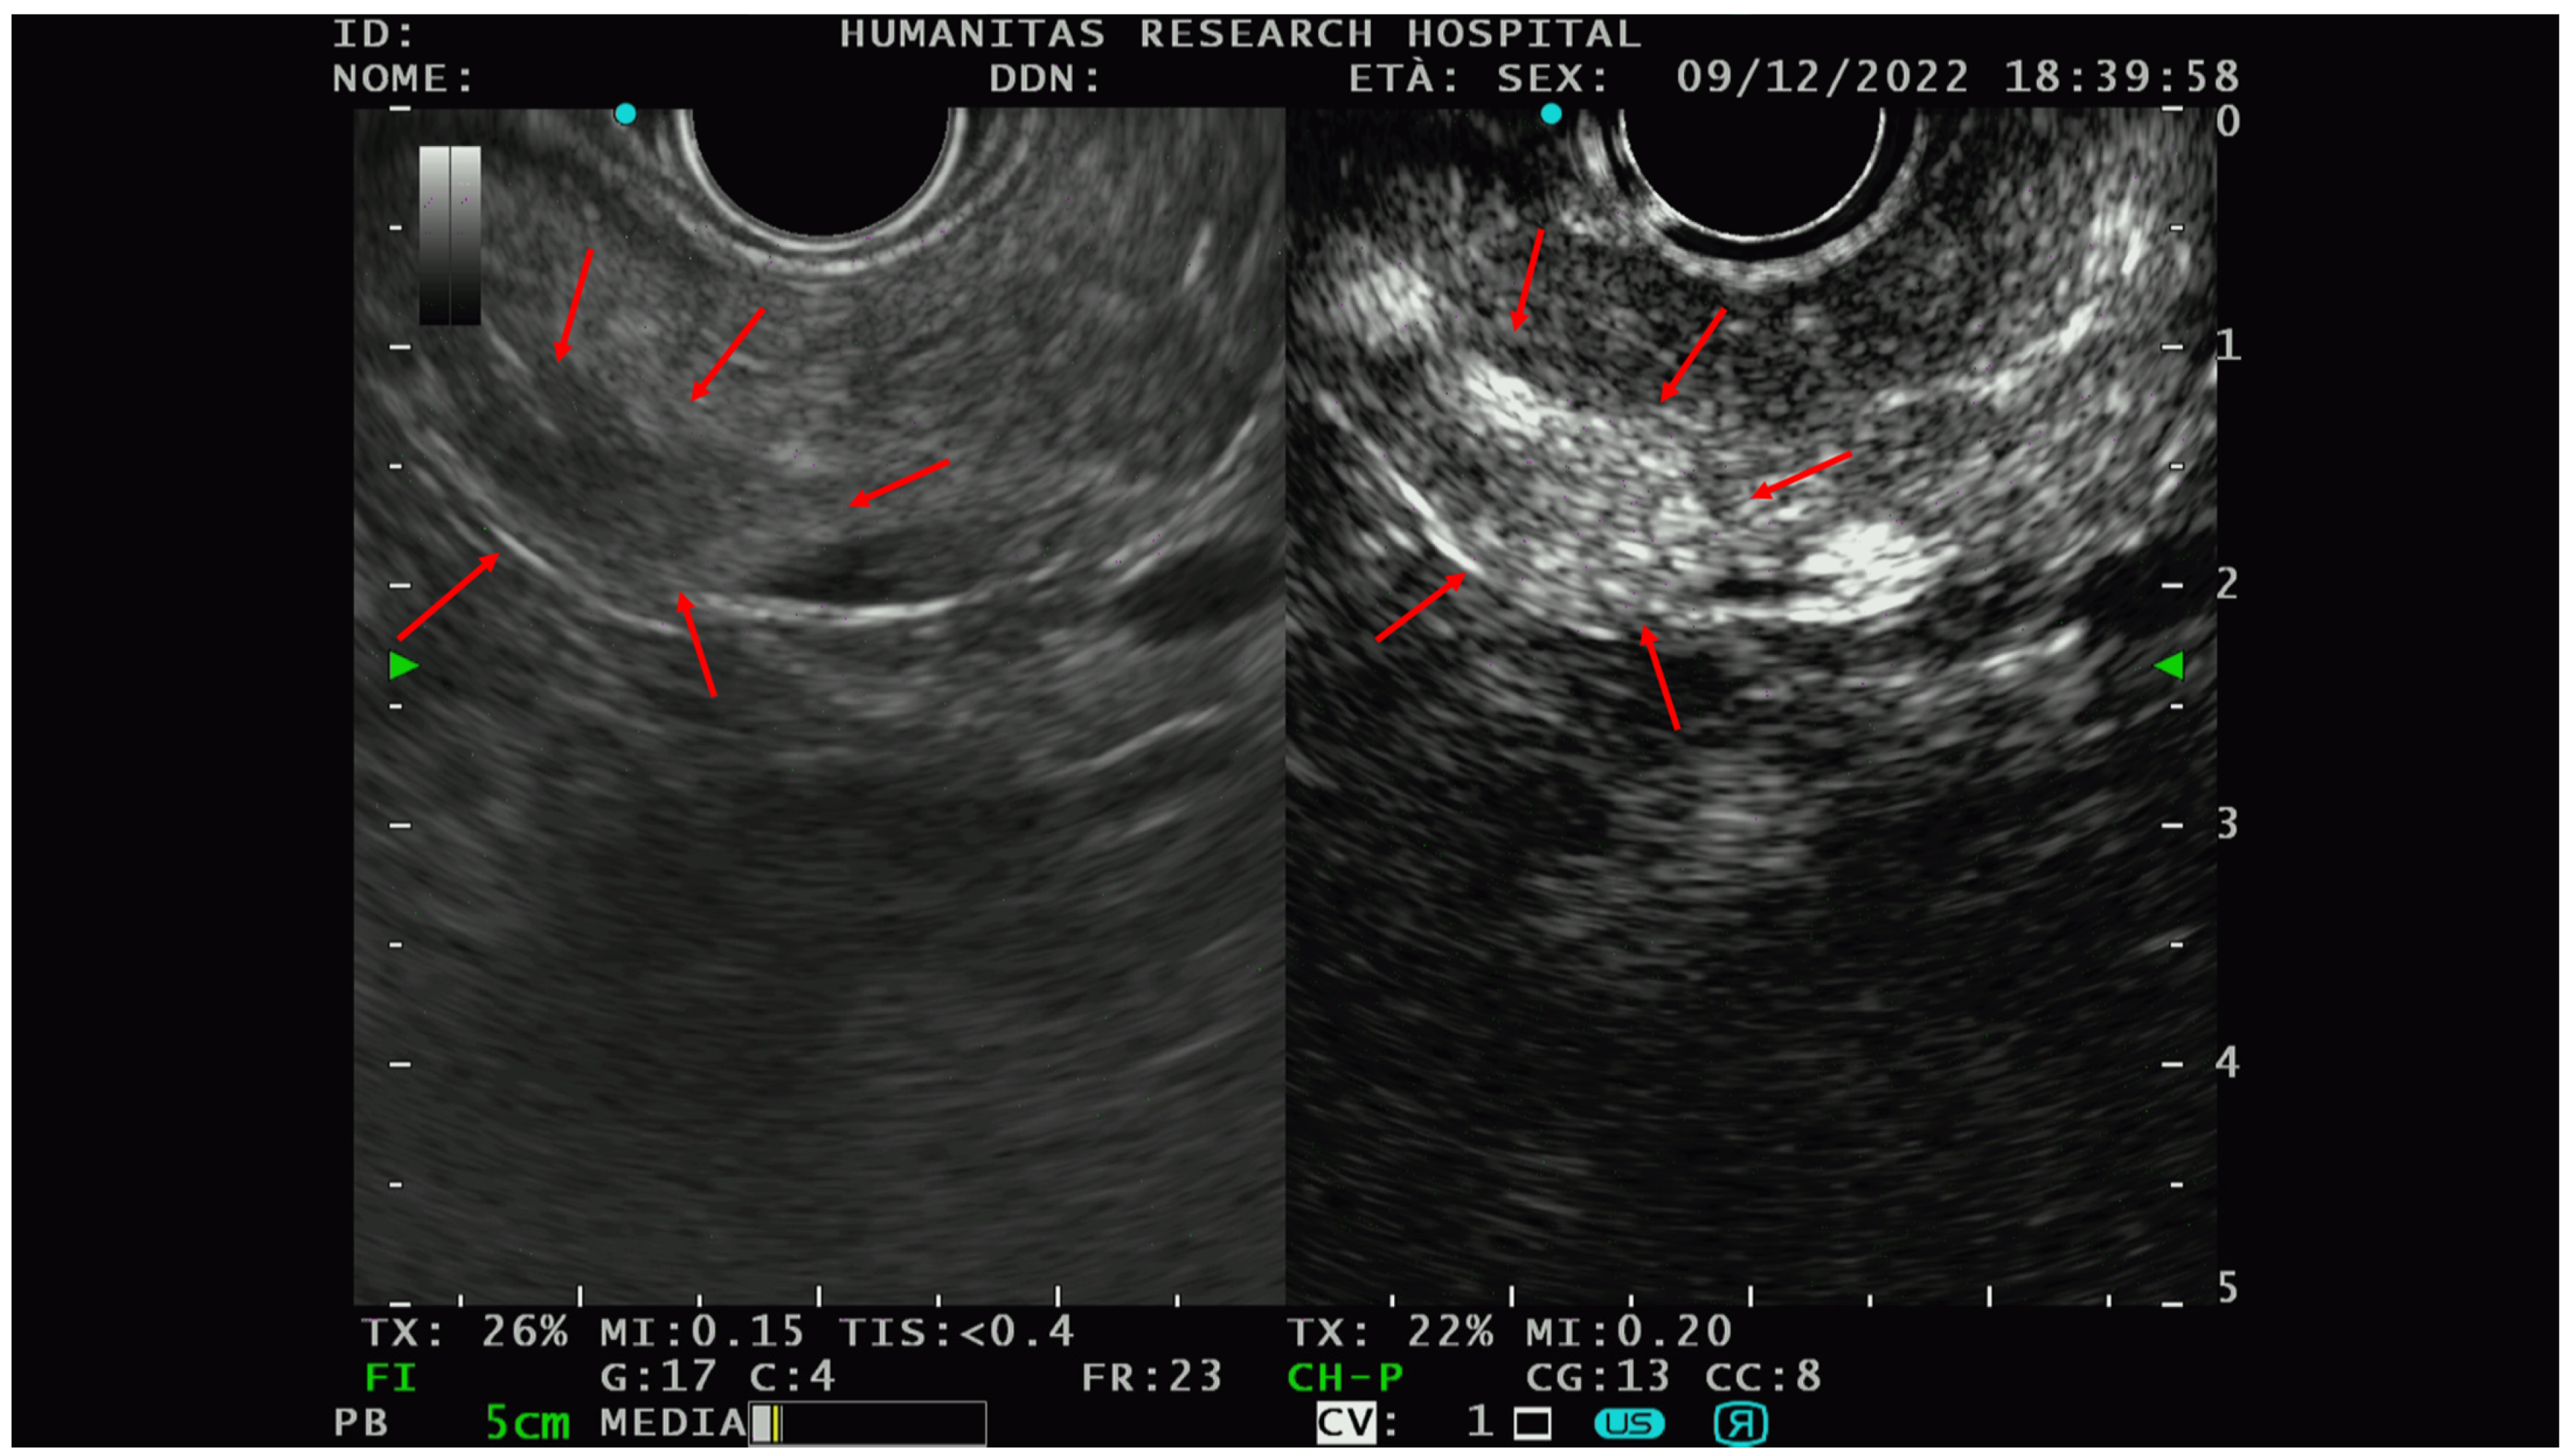

On EUS, basal analysis PTENs typically appear as homogeneous hypoechoic lesions with regular margins (Figure 1); sometimes they can have a cystic appearance [22] while in the most advanced cases, they can lose these characteristics, acquiring features more similar to pancreatic adenocarcinoma [23].

Figure 1.

A hypoechoic lesion of 21 mm with regular margins (identified by the blu +) and an ipoechoic appearance; at histopathological analysis the lesion was a G1 NET.